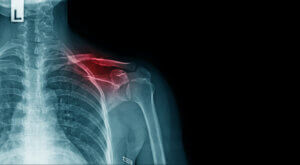

- Crushed or multiple bone fractures